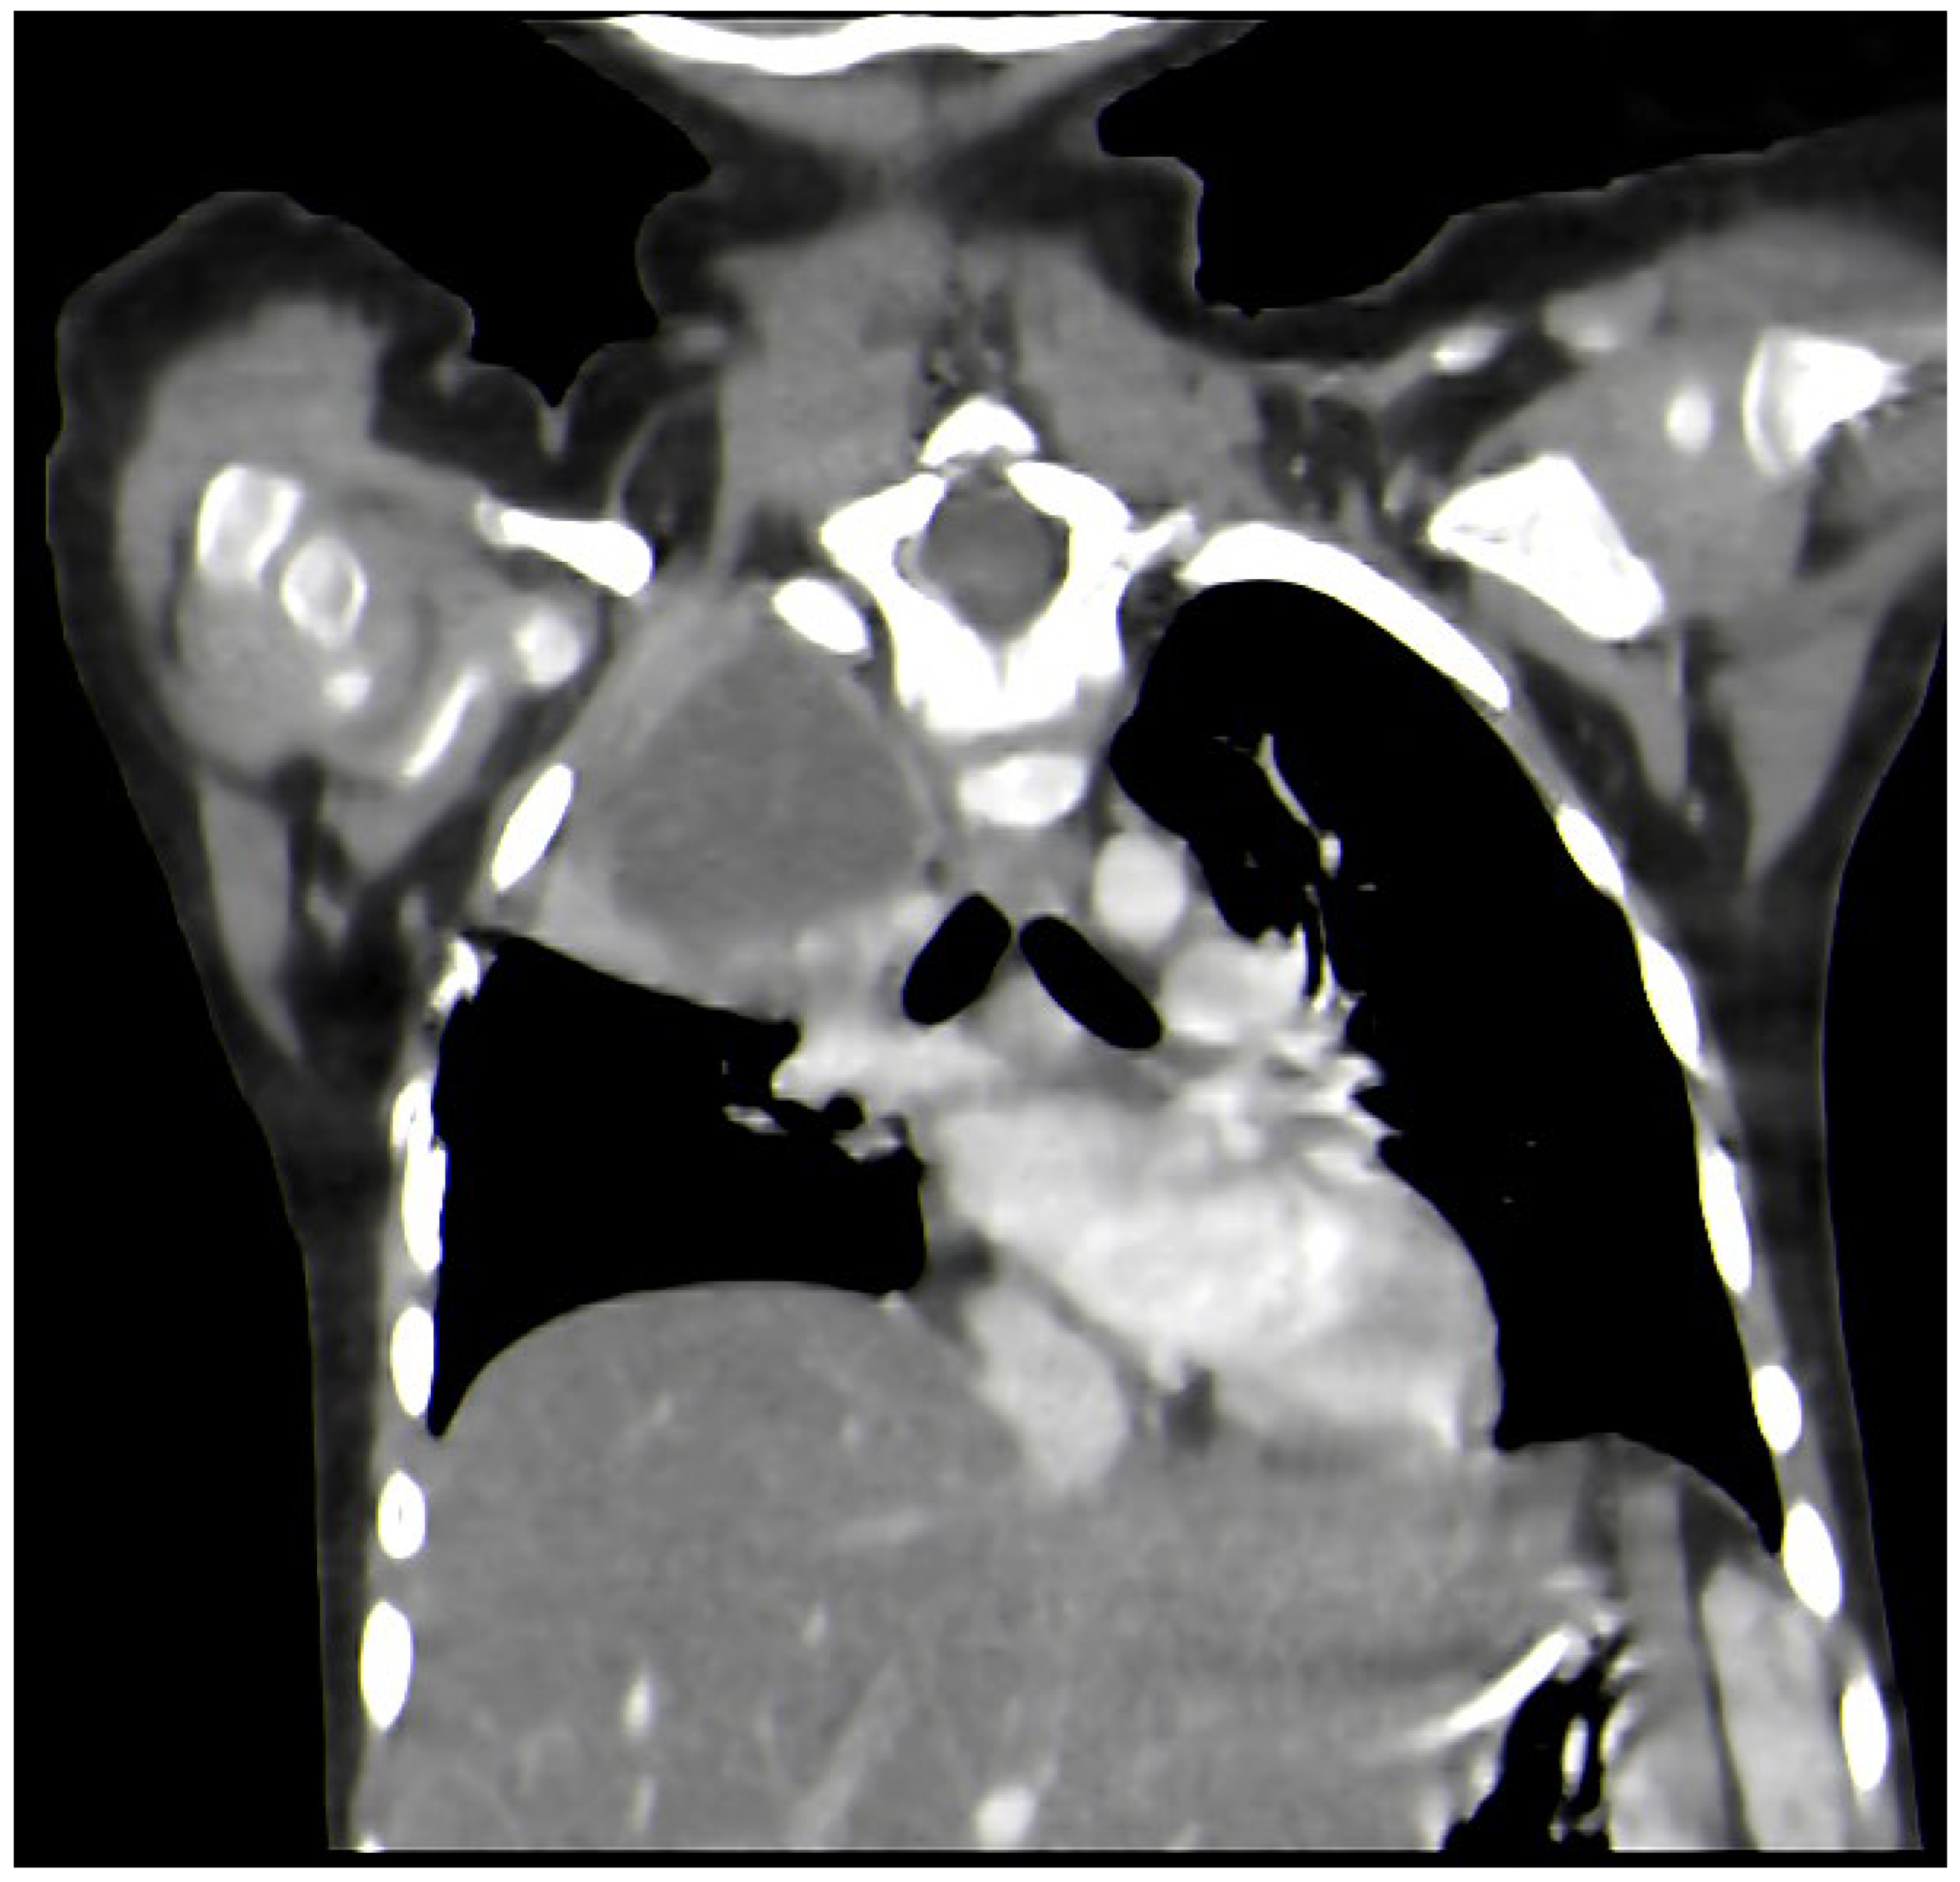

2. Case Report